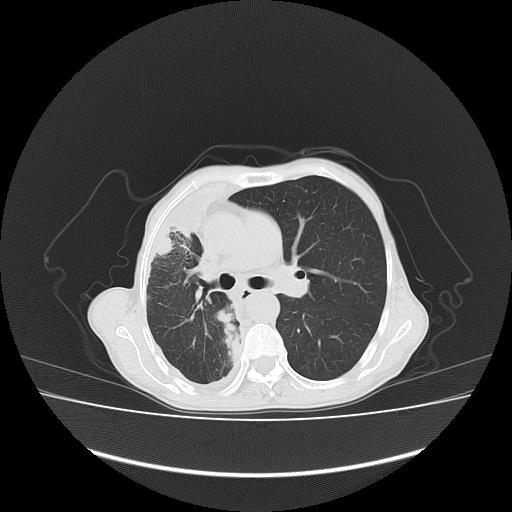

可见多发肺内病灶,且胸膜病灶较多有圆球状而非丘状,多考虑胸膜转移瘤伴胸腔积液,右侧胸廓缩小固定,且部分病灶呈丘状,尚不除外恶性胸膜间皮瘤伴肺内转移

恶性胸膜间皮瘤伴肺内转移可能性大;或胸膜、肺内均为转移瘤,左肺下叶亦见多发小结节影。

胸膜转移瘤  包裹性胸腔积液  肺内转移

右胸腔结节均考虑来自胸膜(部分来源于叶裂),考虑胸膜间皮瘤或转移瘤.